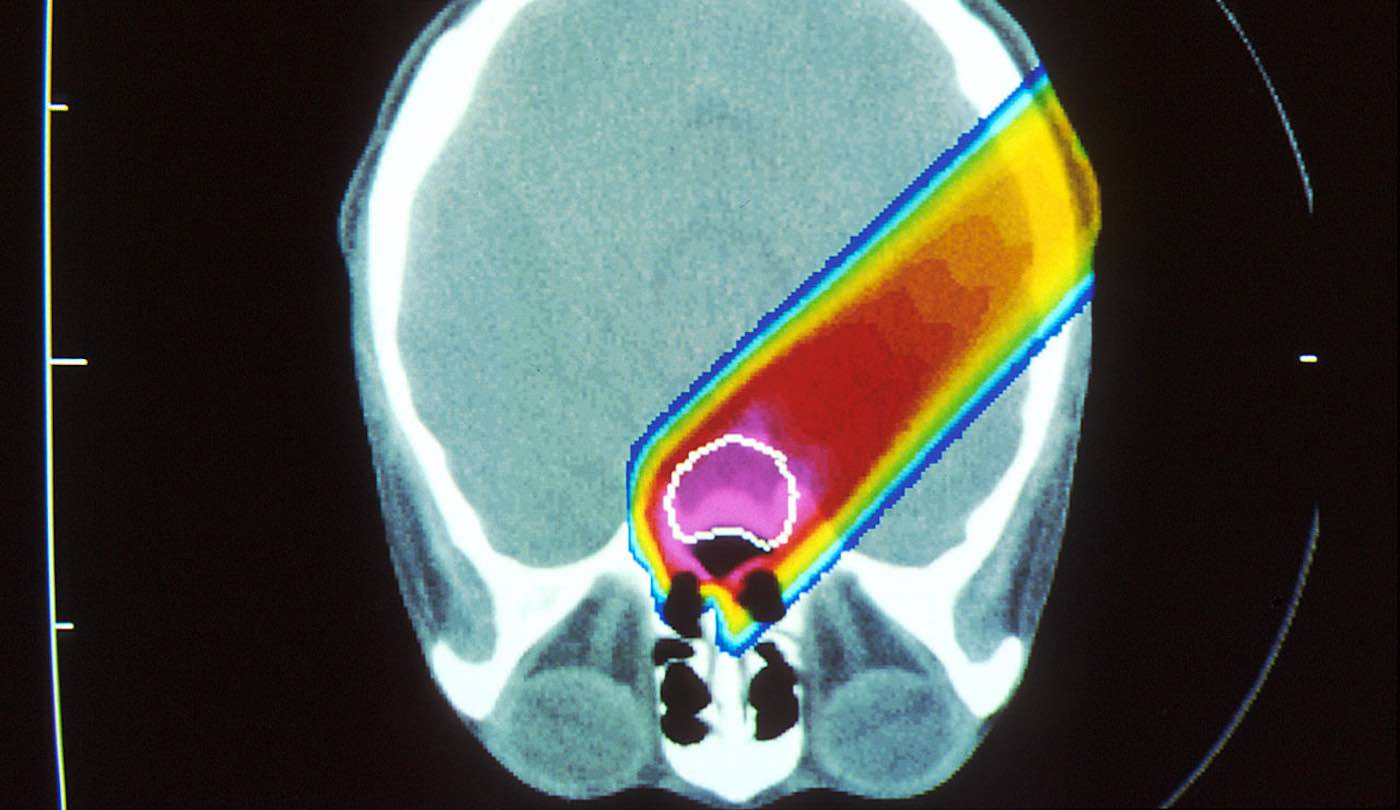

Unlike traditional photon radiation using x-rays, proton radiation therapy (PRT) is a non-invasive, precise cancer treatment that uses a beam of protons moving at very high speeds to destroy the DNA of cancer cells, killing them and preventing them from multiplying.

Highly targeted, PRT has significant promise for treating tumors in very young children and may reduce radiation exposure to healthy, developing tissue that may result in lifelong impacts.